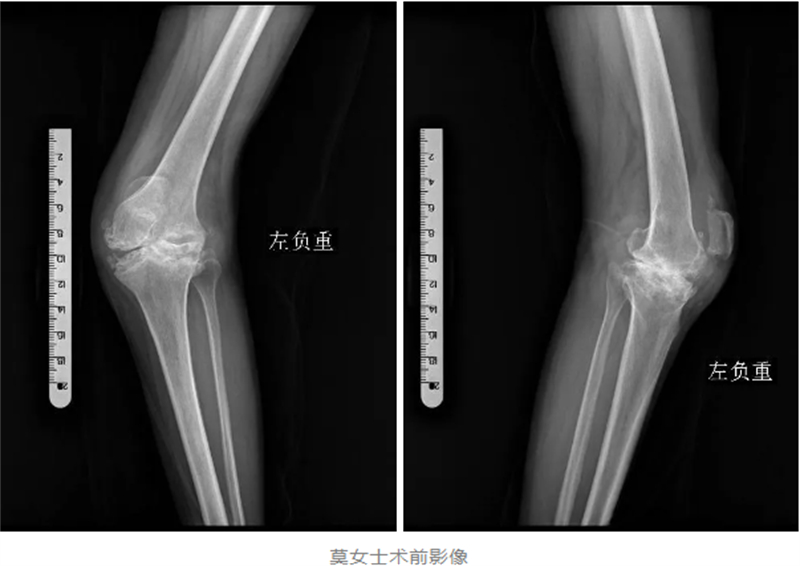

入院后,經(jīng)過(guò)詳細(xì)的檢查,醫(yī)生發(fā)現(xiàn)莫女士的左膝關(guān)節(jié)已經(jīng)嚴(yán)重破壞,甚至達(dá)到了毀損的程度。韋健博士介紹,對(duì)于常規(guī)的“腿不歪”的嚴(yán)重膝關(guān)節(jié)磨損,用普通膝關(guān)節(jié)假體進(jìn)行人工膝關(guān)節(jié)表面置換手術(shù)即可解決行走及疼痛問(wèn)題,但對(duì)于莫女士這種罕見(jiàn)的、嚴(yán)重變形的毀損型膝關(guān)節(jié),普通膝關(guān)節(jié)假體已經(jīng)無(wú)法滿足手術(shù)需求。

對(duì)于莫女士來(lái)說(shuō),這不僅是一次手術(shù),更是她重獲健康、重拾生活信心的關(guān)鍵。因此,韋健博士及其團(tuán)隊(duì)經(jīng)過(guò)充分的討論和周密的術(shù)前準(zhǔn)備,決定采用髁限制型人工膝關(guān)節(jié)假體,為莫女士進(jìn)行一場(chǎng)“美容”手術(shù),幫助她實(shí)現(xiàn)重塑“大長(zhǎng)腿”的夢(mèng)想。